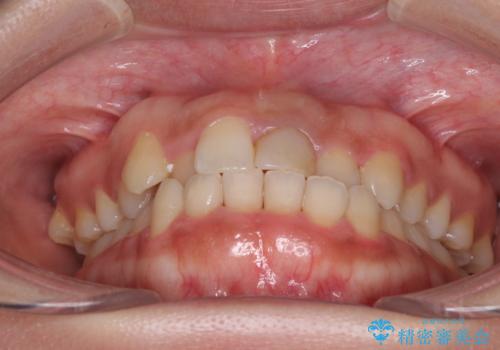

前歯のクロスバイトと変色した歯 ワイヤー矯正とセラミック治療

- 前歯のクロスバイトと神経を取り除いた後に変色してしまった前歯を気にして来院された患者様です。

ワイヤー矯正により矯正治療を行った後に、前歯の補綴治療を行うこととしました。

変色してしまった前歯は、反対側の歯と比べて歯肉が覆い被さっていたため、骨整形を含めた歯周外科処置を行い、歯肉ラインを整えることとしました。